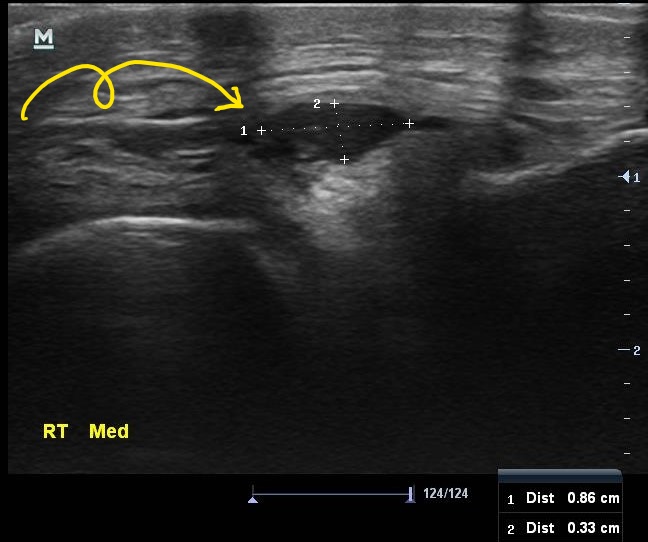

이 환자분의 진짜 문제는 초음파 검사에서 발견되었습니다.

나 : 내측반월판 연골 부위에 물혹이 하나 생겨있습니다.

나 : 네 결절종이라고 하는 건데요... 무릎을 굽히실때 이게 주변 조직을 누르면서 통증이 발생한듯 합니다.

나 : 초음파 보면서 주사기로 물혹속 내용물을 제거해봐야 할거 같습니다.